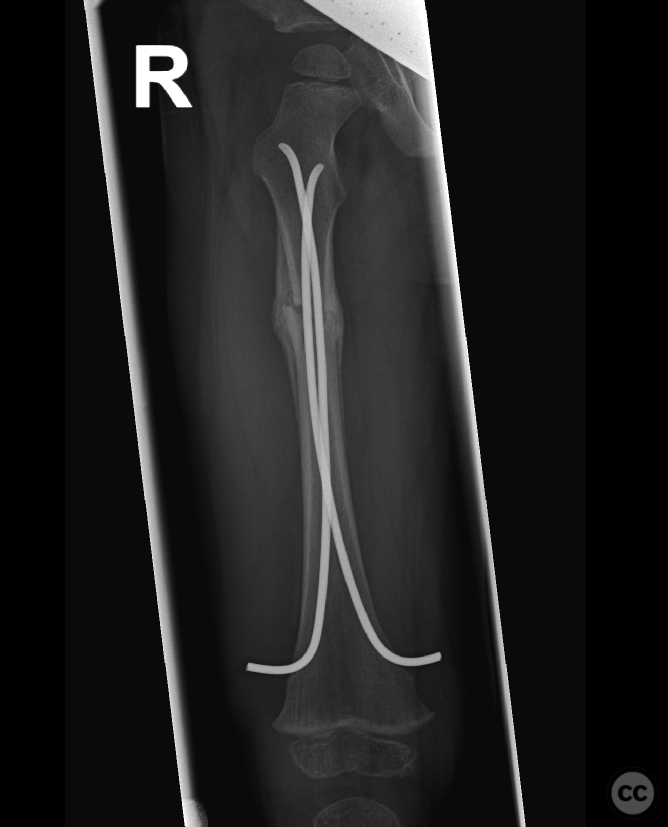

Femoral diaphyseal spiral fracture in 22...

Schleswig Holstein, Germany

Paediatric - PCCF